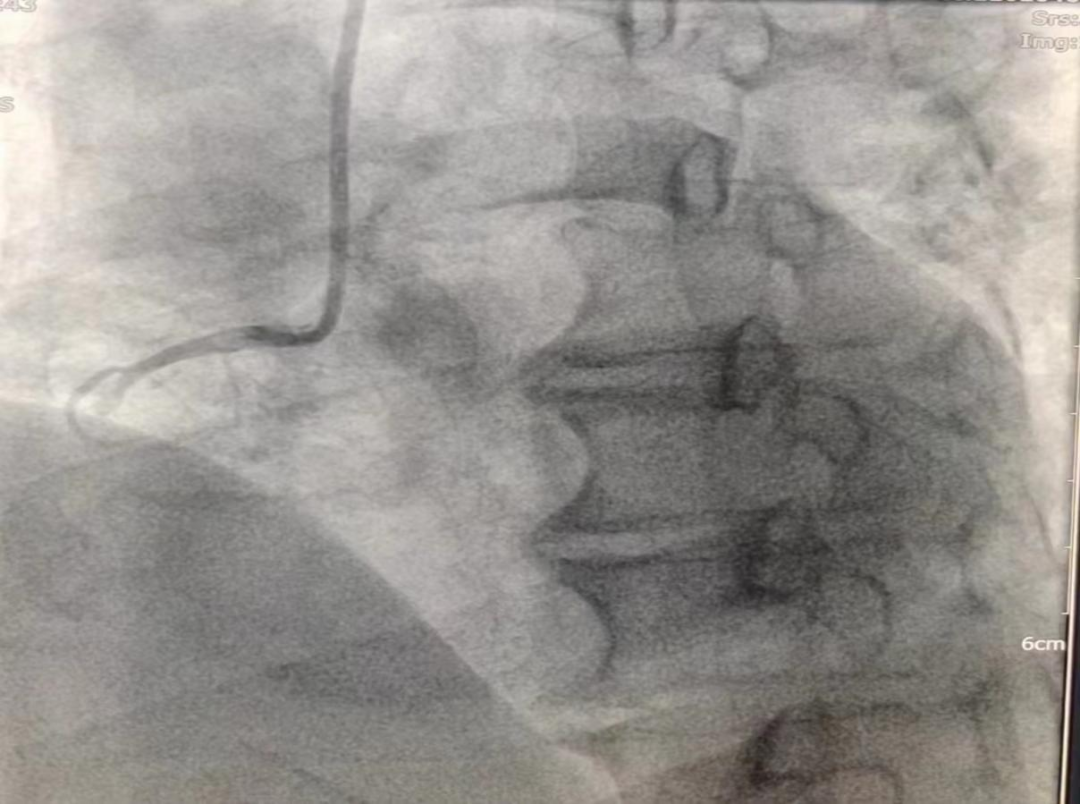

女性患者,49歲,突發暈厥急診我院,經診斷為:冠狀動脈粥樣硬化性心臟病、2型糖尿病。導入造影導管行冠狀動脈造影示:冠狀動脈分布呈左冠優勢型,LM未見明顯狹窄,血流TIMI3級;LAD全程多發斑塊,中段狹窄約60%,遠端狹窄約50%,D1未見明顯狹窄,血流TIMI3級;LCX未見明顯狹窄,血流TIMI3級,RCA近端狹窄約50%,中段發出圓錐支后完全閉塞,血流TIMI0級,急診開通血管并充分擴張,殘余狹窄仍然嚴重。在與患者及家屬溝通時,其了解得知臨床有一種新型的可吸收支架,植入體內后支架能完全被降解和吸收,希望能用這種新型的支架進行手術治療。由于生物可吸收支架有著嚴格的適應癥,因此經過嚴格篩選評估,最終對患者進行了Xinsorb生物可吸收支架置入術。支架植入術前經過充分預擴張,按照規范的可吸收支架操作流程,快速送入可吸收支架到病變部位,精準定位后14個大氣壓釋放,生物可吸收支架后擴球囊擴張。充分球囊后擴張,以保證支架貼壁良好,血流速度正常,造影完美,手術順利結束。

(圖為右冠病變術前影像)

(圖為生物可吸收支架置入術后影像)